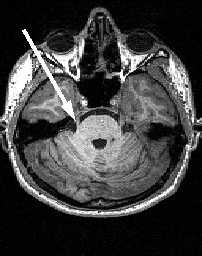

Кзади от моста и продолговатого мозга расположен мозжечок . Со стволом мозга он соединен верхней, средней и нижней ножками мозжечка. Состоит мозжечок из срединно расположенного червя и парных полушарий.

МРТ головного мозга. Аксиальный срез. Мозжечок (CV- червь мозжечка, CH - полушарие мозжечка).